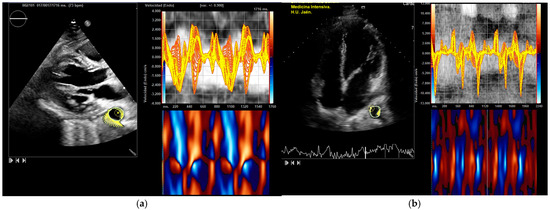

- Ruiz-Bailén, M.; Hidalgo-Martín, J.; Manetsberger, J.; Clau-Terré, F.; Martínez-Gámez, J.; Dagomar Lohman, J.; Lavilla-Lerma, M.L.; Matallana-Zapata, D.F.; Ballesteros-Barroso, M.; Rivera-Fernández, R.; et al. Usefulness of vector velocity imaging in the descending thoracic aorta. Med. Intensiv. Engl. Ed. 2025, 502224. [Google Scholar] [CrossRef]